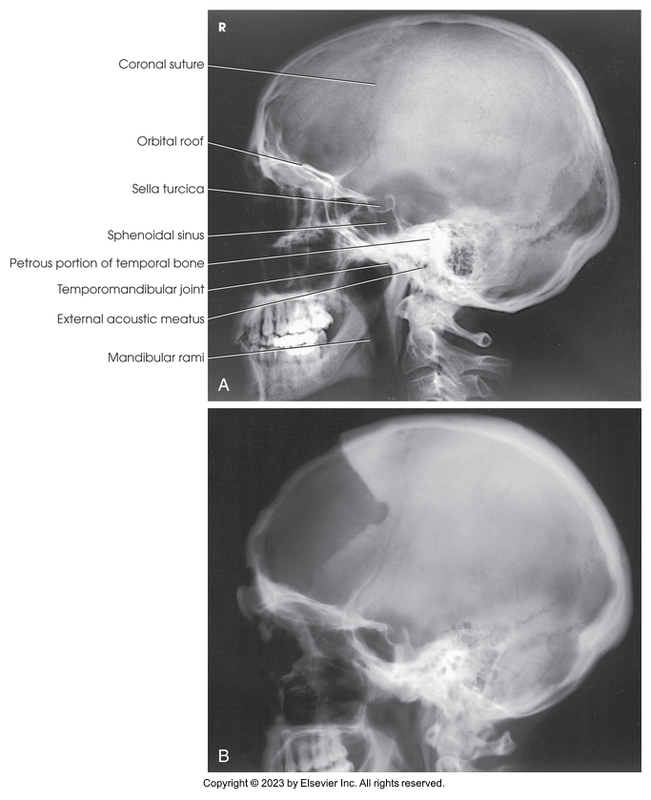

Lateral Projection of the Skull

Lateral projection of skull